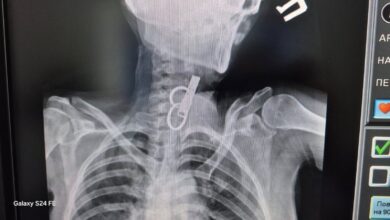

Стан новонародженої дівчинки, яку залишили в під’їзді багатоповерхівки у Тернополі, поступово стабілізується.

Наразі дитина перебуває під наглядом лікарів обласної дитячої клінічної лікарні.

“Стан вже трошки покращився, але ще важкий. Вже зняли інкубацію, є позитивна динаміка”, – наголосив Володимир Семерез.